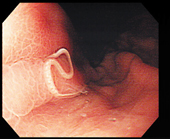

症例3.胃アニサキス症(図9,10)

「みる」患者は38歳,女性.心窩部痛で来院,食歴を問うと前日にイワシの酢漬けを摂取していた.

「見る」超音波検査では心窩部痛でもあり胃を見ると胃壁の肥厚が見られ,その壁に細い2本線が断片的に見られた.

「診る」生魚の摂取後にみられる心窩部痛では胃壁に肥厚を見たら胃アニサキス症を考える.本症例では,胃壁の肥厚は主体が粘膜下層であり,アニサキス幼虫が胃壁に刺入し即時型過敏反応を生じていると考えた.本疾患を診るには,臨床所見として生魚の摂取の有無が重要であるが,同時に胃壁に見られるアニサキス幼虫を捉えて証明しなければならない.アニサキス幼虫の超音波像は細いチューブ様の2本線である.しかし,虫体は体幅が0.5〜1.0mmほどしかなく,また多くの場合はとぐろを巻いている.このため,高周波リニア型探触子を用いてさらに拡大した手法による観察でも虫体は断片的な部分としてしか描出されないことに注意する.なお,本疾患は胃では生食3〜8時間後,腸管は2〜4日後に腹痛を生じることが多く,寄生部位が腸管なら腸閉塞を伴うことも多い.